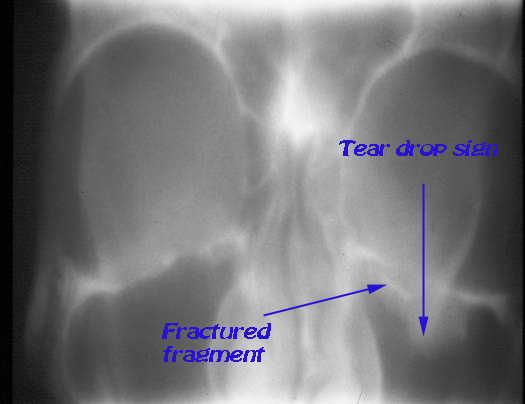

X -ray paranasal sinuses: May show the classical "tear drop sign" of prolapsed orbital contents. The fractured fragment may also be visible. The corresponding maxillary sinus may appear hazy due to the presence of hemosinus.

X-ray PNS showing tear drop sign